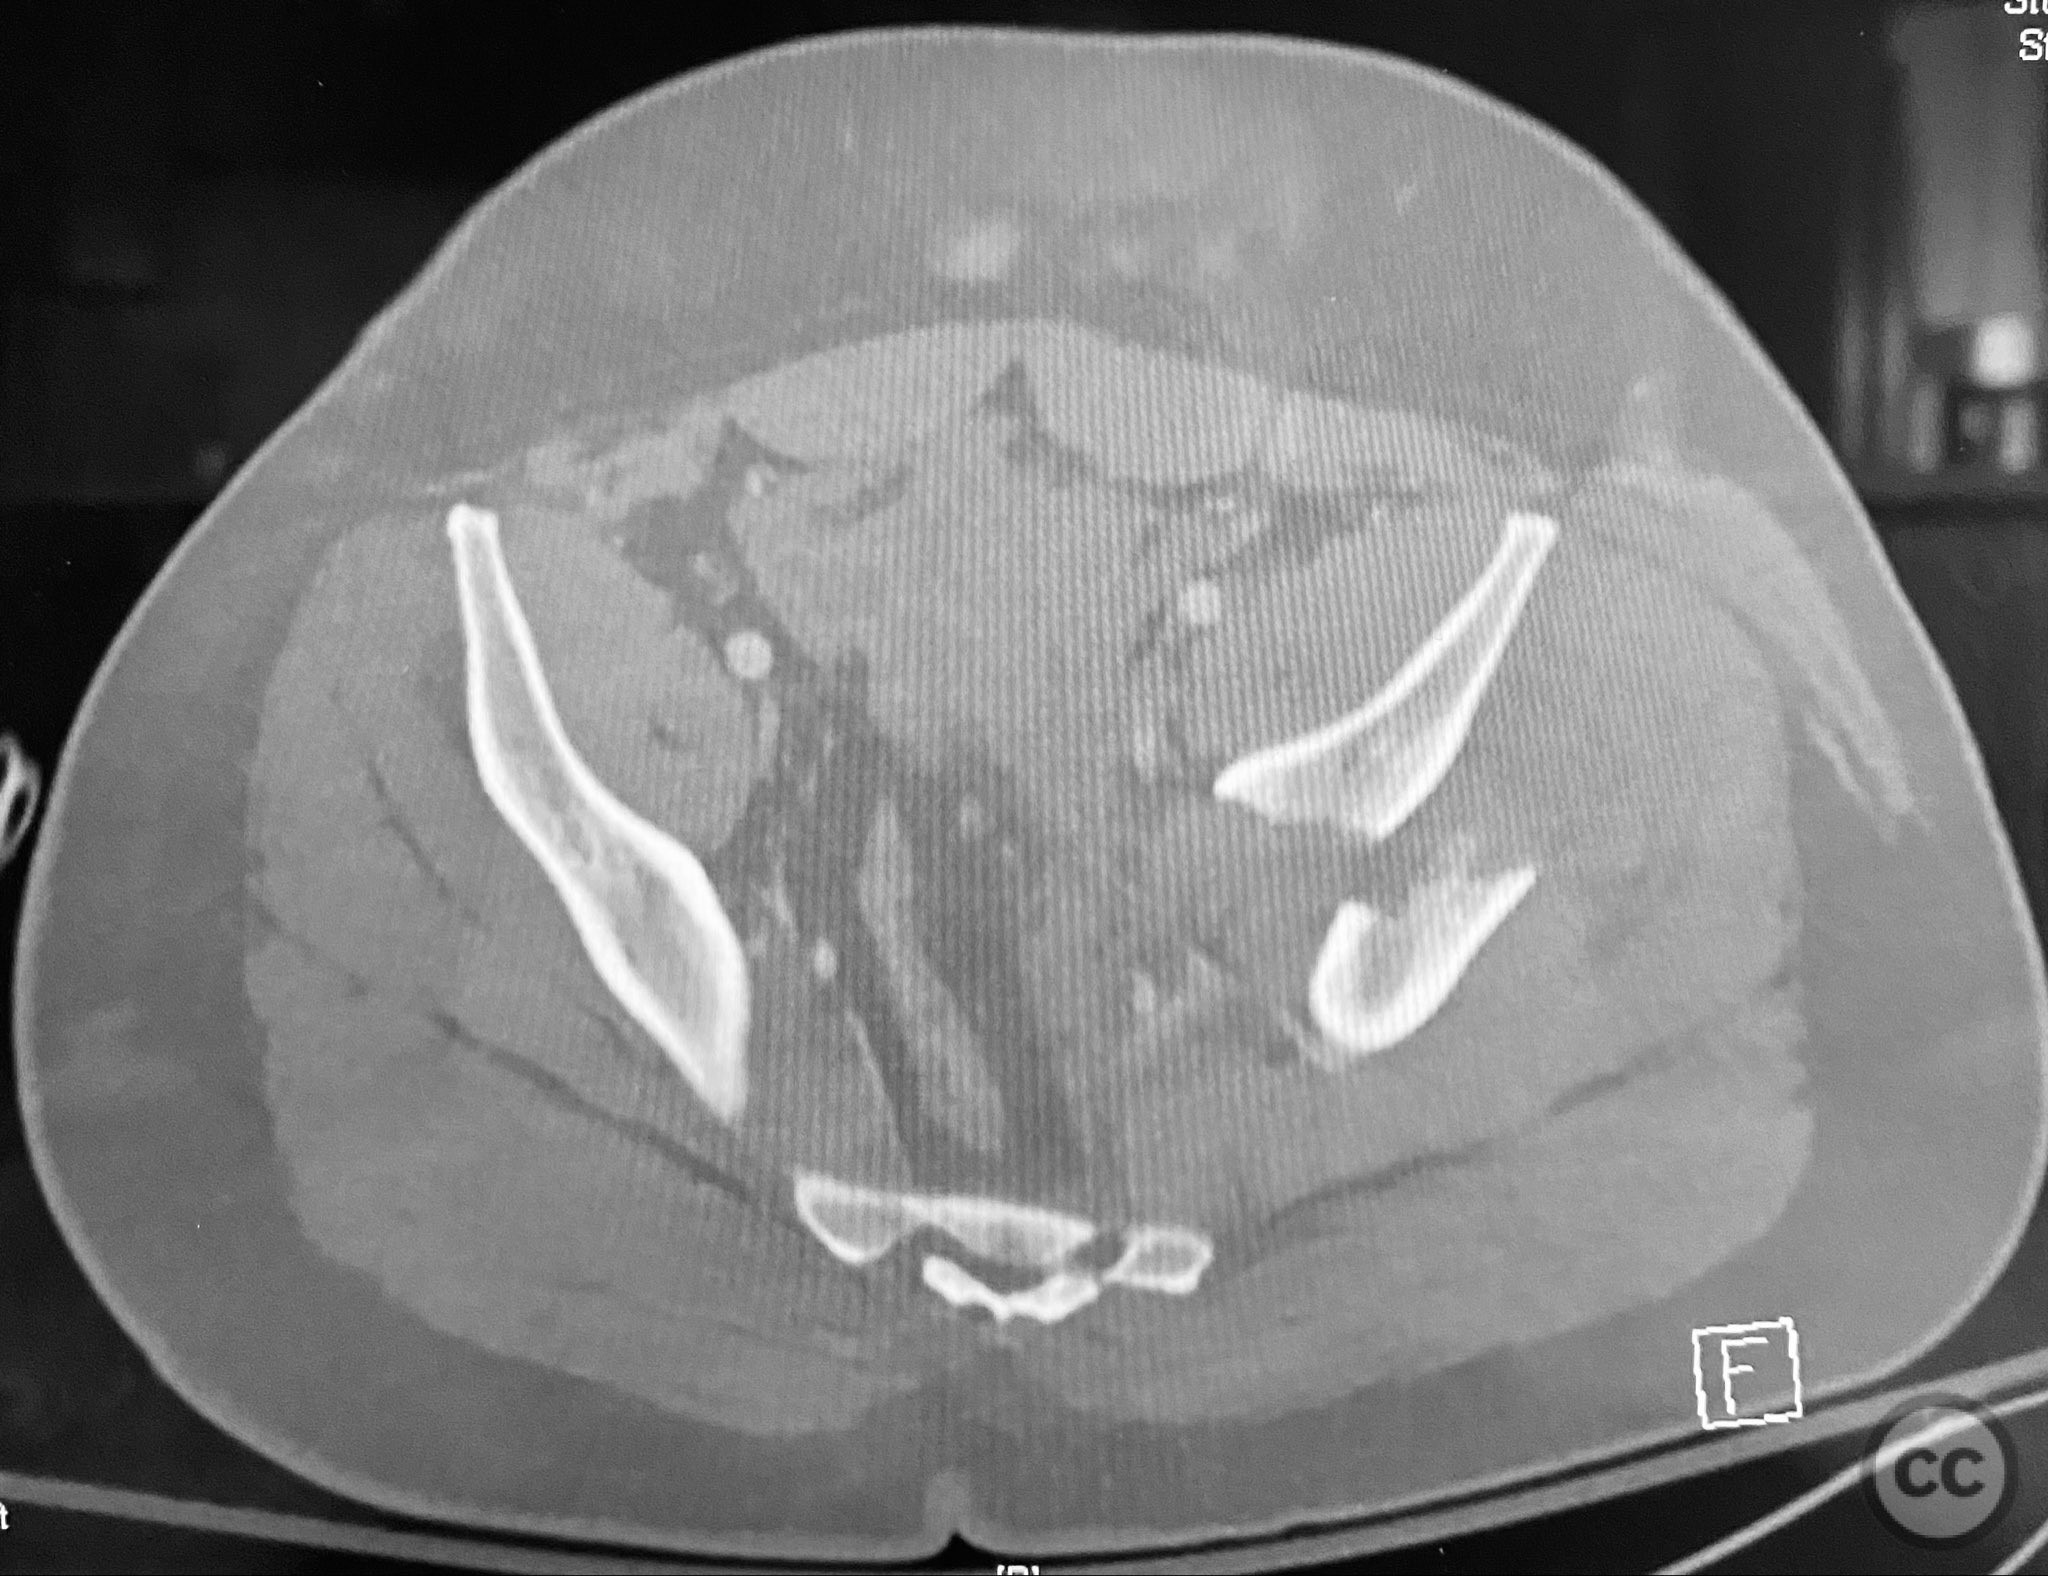

Clinical and radiological findings:  A patient presented with a displaced associated both column acetabular fracture, characterized radiographically by the presence of the "spur sign" on the anteroposterior (AP) pelvis film, indicating the caudal aspect of the intact ilium exposed by medial displacement of the articular fragments. The spur was more clearly visualized on the obturator oblique rendered image. Axial computed tomography (CT) images demonstrated the intact ilium, medially displaced anterior column (AC) and posterior column (PC) fragments, and provided detailed visualization of surrounding soft tissues, including vascular structures enhanced by contrast. Multiplanar CT reconstructions (axial, sagittal, coronal) and 3D renderings were utilized for comprehensive fracture and soft tissue assessment. The patient’s overall clinical condition was a significant factor in surgical planning.